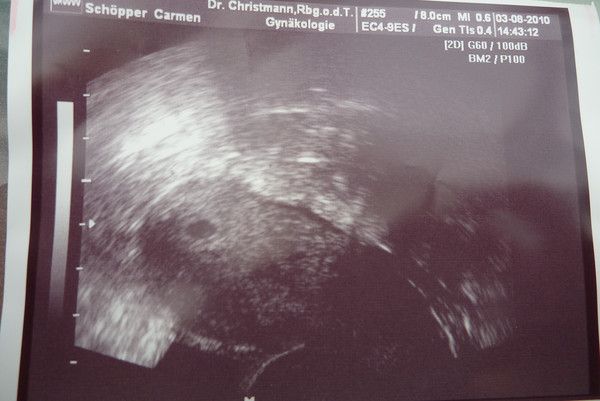

1.US_samulu_ET01042010

25.08.2010

zusehen ist schön der Embryo SSL 18mm; Markierung + ist Herzchen; rechts unten Nabelschnur und noch Dottersack

daraus ergibt sich eine Summe von ALLES OK in der 9.SSW (SSW8+5T)